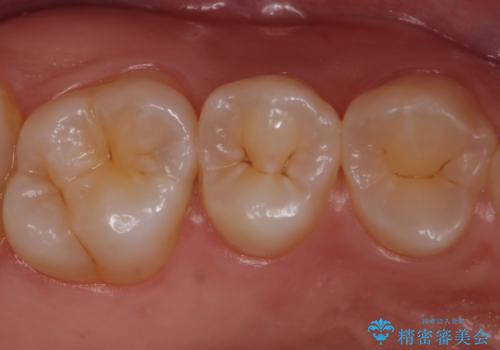

歯と歯の間の虫歯 セラミックインレーでの治療

- 矯正前の虫歯治療です。

歯と歯の間に虫歯があったためセラミックインレーで治療をしていきました。

- 右上6 セラミックインレー 77,000円費用は治療当時の料金となります